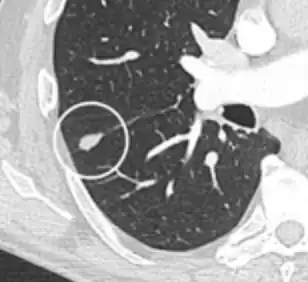

- A lung nodule abutting a pulmonary cyst is a rare finding, yet indicating cancer.[9]

- Bubble-like lucencies in the nodule indicate cancer:[9]

.png)

- Vascular convergence is where vessels converge to a nodule without adjoining or contacting the edge of the nodule, and is mainly seen in peripheral subsolid lung cancers.[9] It reflects angiogenesis.[9]